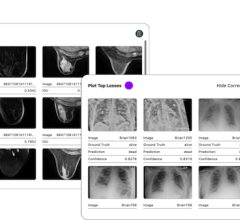

Nov. 6, 2025 — Gradient Health and DataFirst have announced a strategic partnership designed to bridge the gap between ...

Radiology departments have many different needs and face a wide variety of challenges that can impact their departments ...